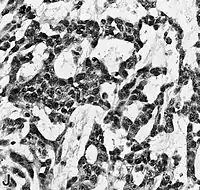

Examen microscópico

El glioblastoma es una neoplasia anaplásica de la glía compuesta por células tumorales astrocíticas pobremente diferenciadas, polimórficas, con marcadas atipias nucleares y una intensa actividad mitótica. Otras características peculiares a fines diagnósticos son también la marcada proliferación microvascular y la presencia de necrosis. Como sugiere el adjetivo "multiforme", la morfología histológica del glioblastoma es extremadamente variable, con células redondeadas, en forma de huso, de dimensiones más bien pequeñas o muy grandes. Mientras que algunos glioblastomas muestran un alto grado de polimorfismo celular y nuclear, con numerosas células gigantes plurinucleadas, otros presentan una conformación caracterizada por una celularidad intensa, pero más bien repetitiva.

La naturaleza astrocítica de la neoplasia puede resultar bastante fácil de identificar, al menos localmente, en algunos tumores, pero difícil de reconocer en otros, debido al alto grado de anaplasia. La heterogeneidad de región a región del glioblastoma es relevante y dificulta el diagnóstico en muestras limitadas, como las obtenidas por biopsia estereotáxica[69] (véase la fotografía en Cirugía). A pesar de la presencia predominante de células poco diferenciadas, en algunos puntos se pueden distinguir astrocitos neoplásicos más diferenciados. Esto es particularmente cierto en los casos de glioblastoma como resultado de la progresión de un astrocitoma difuso (grado II de la escala OMS). La transición entre zonas que aún poseen diferenciación astrocítica reconocible y zonas de alta anaplasia celular puede ser continua o repentina. Un cambio brusco en la morfología refleja habitualmente la aparición de un tumor diferente, fruto de la adquisición de una o más alteraciones genéticas adicionales.[70]

En el contexto de la neoplasia se observan grandes áreas de necrosis, rodeadas de núcleos dispuestos paralelos entre sí, formando "empalizadas" típicas. Se encuentra una marcada proliferación de células endoteliales con formación de numerosos vasos, a veces con apariencia de montón o madeja. Algunos tienen pared hialina y otros están trombosados. La proliferación endotelial, sin embargo, no es difusa sino focalizada en algunos puntos. Alrededor de la neoplasia se pueden encontrar zonas de astrocitos gemistocíticos (astrocitomas difusos de grado II).[11][60]